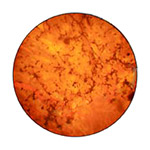

Ocular Histoplasmosis Syndrome

Caused by a fungus commonly found in certain dust and soil.